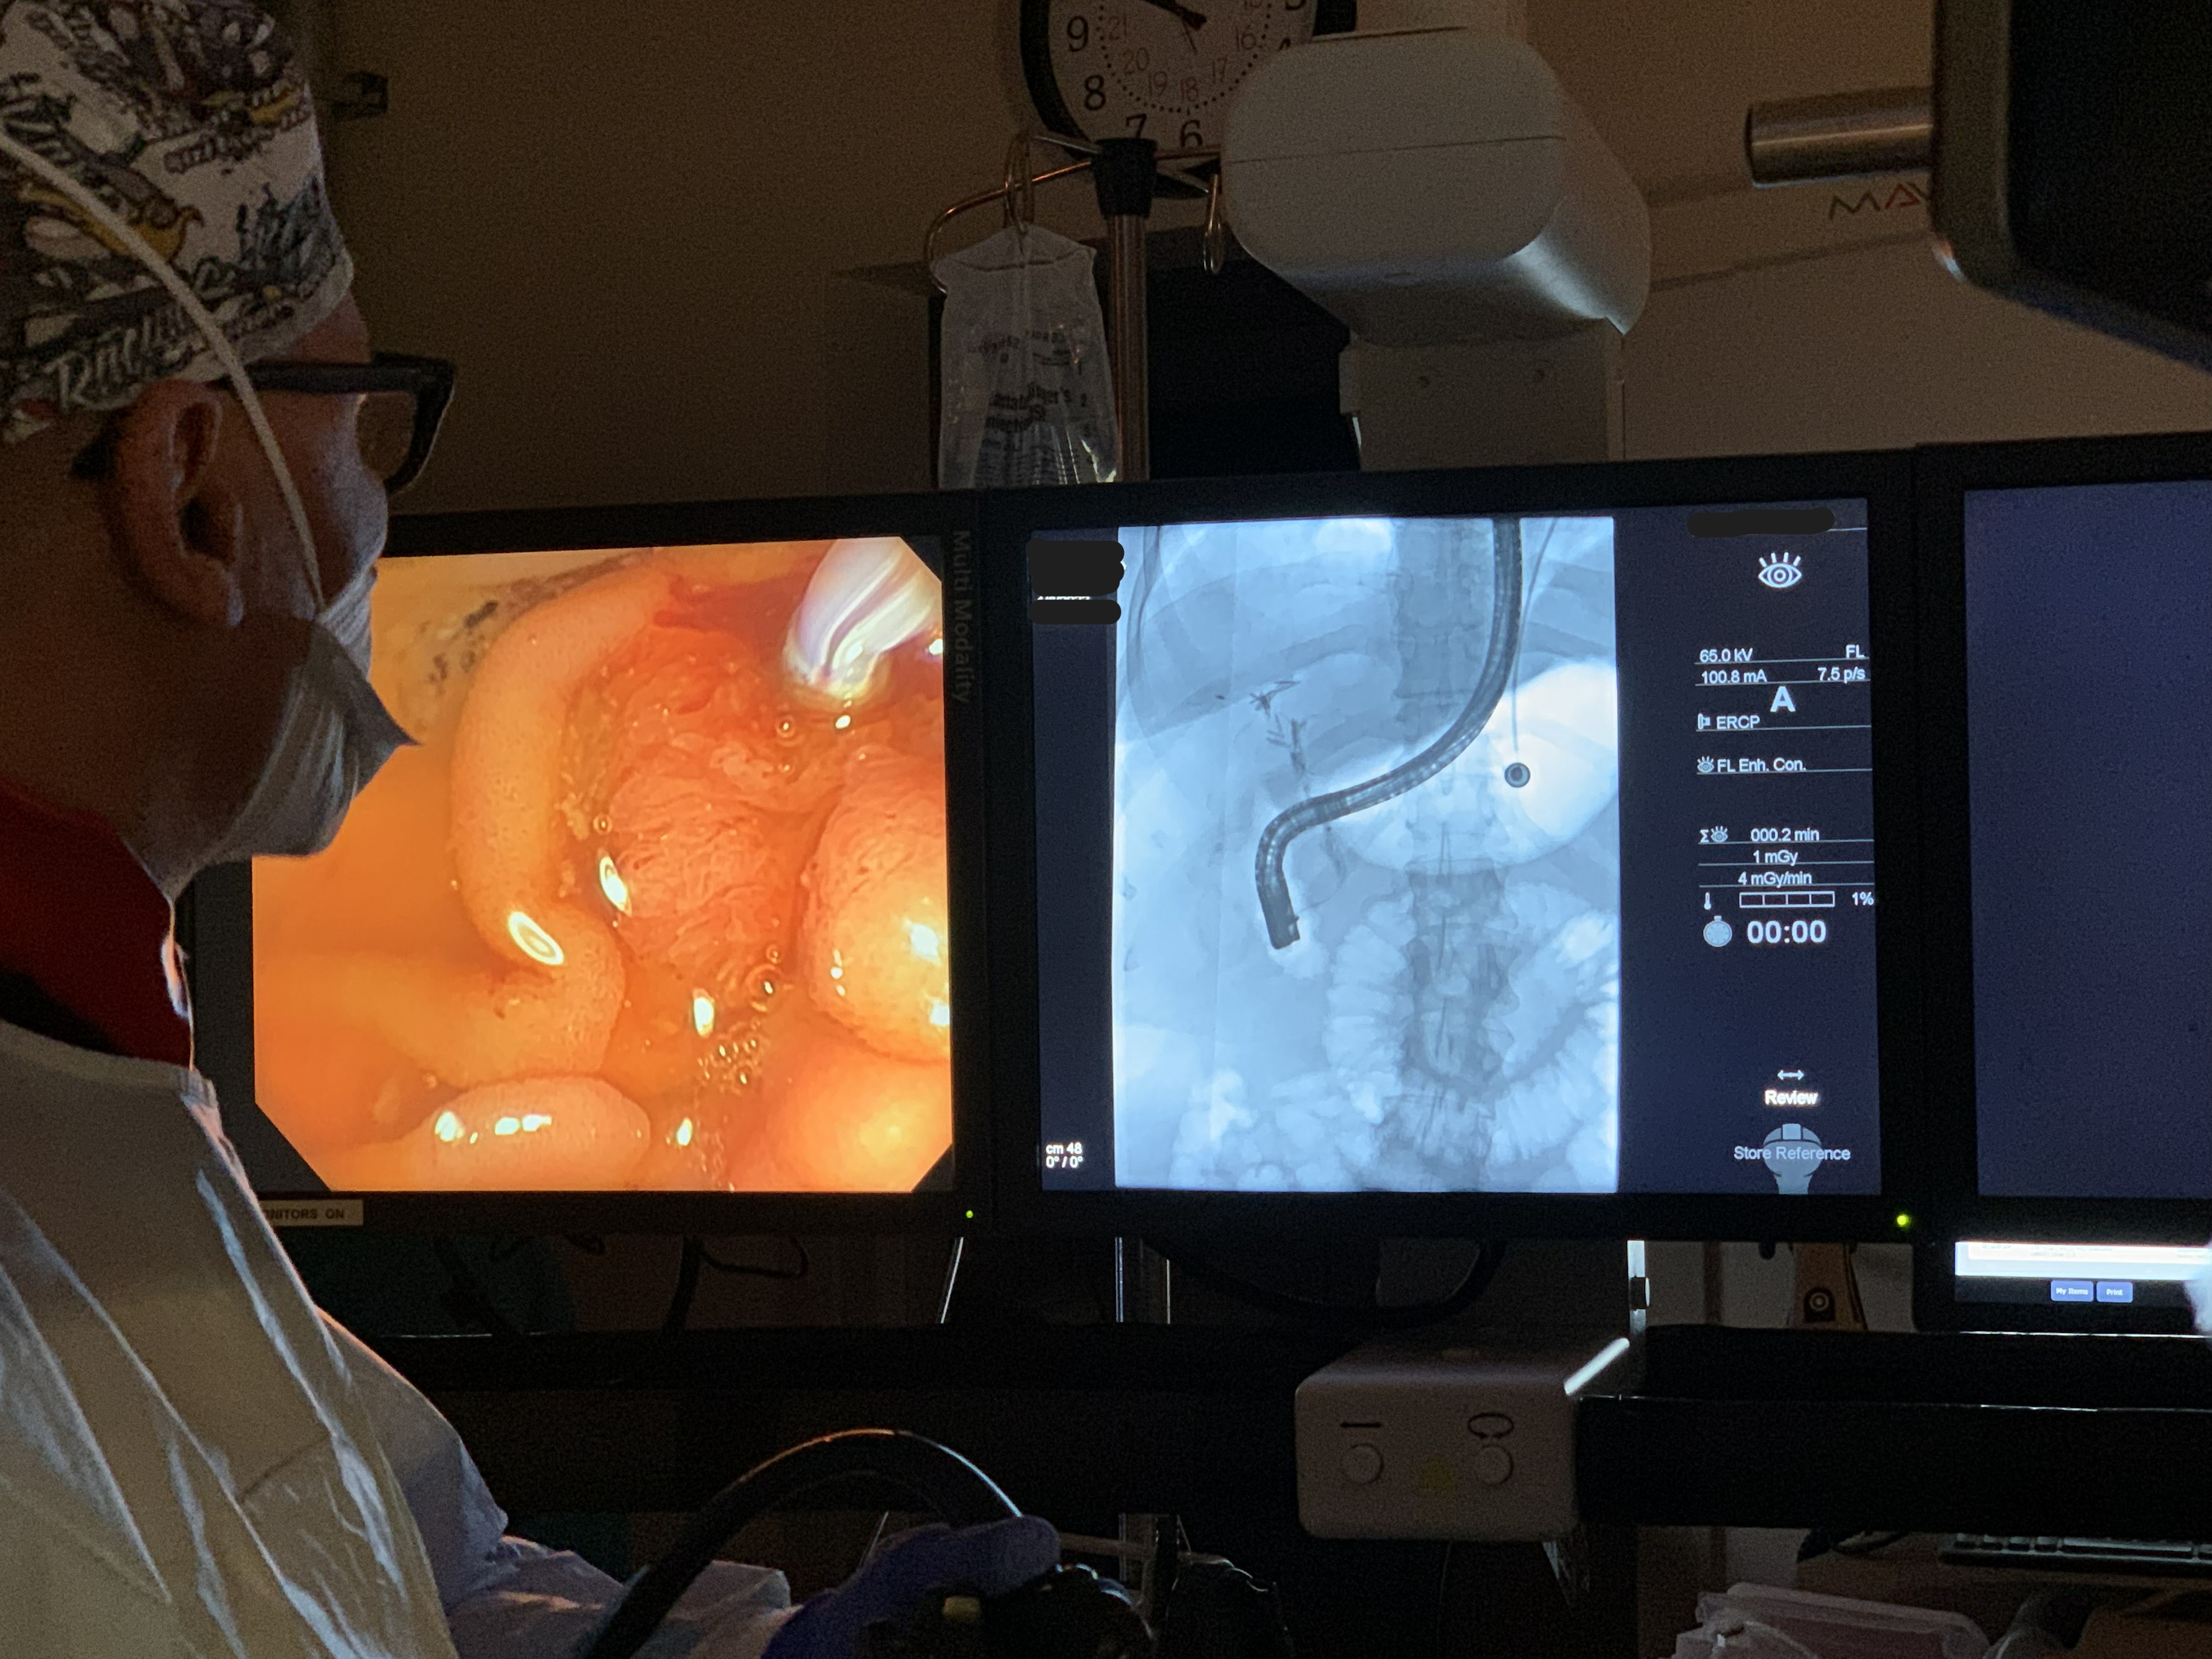

Endoscopic GI Surgical Actuator

Working alongside Dr. Todd Baron and Dr. Lisa Gangarosa at UNC Hospital's Advanced Endoscopy Fellowship, our team identified a clinical need: existing endoscopic tools create post-surgical complications that a redesigned actuator geometry could reduce. I led a team of eight through three years of design, prototyping, and verification — beginning with OR shadowing to understand the procedure environment firsthand.

The design process ran from clinical needs-statement development through ideation sketches — specifying PTFE sleeves, titanium construction, ø2mm working channel geometry, and shape-memory alloy actuation rings — to full parametric CAD and a working proof-of-concept prototype with embedded electronics and an OLED UI displaying power level, machine history, and current position.